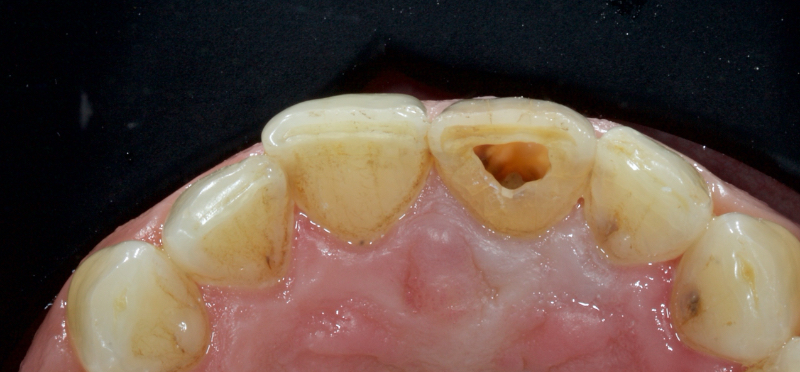

Historically, discolored anterior teeth were treated with indirect ceramic restorations, such as crowns or veneers. This can be illustrated in the case shown in Figure 1, where the discolored left central incisor (2.1), along with two other incisors, was treated with lithium disilicate ceramic veneers (Fig. 2). More recently, direct composite materials that incorporate specialized “opaquers” have also been utilized for treatment.